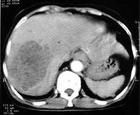

CT常見3~10毫米的低密度區,小於2毫米的病灶CT很難顯影。

頭部磁共振能更好的明確梗塞的部位、大小及新舊程度。